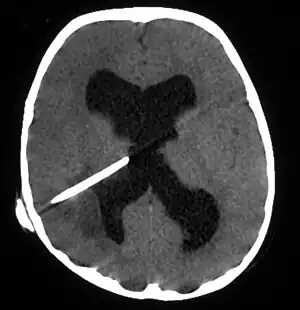

CT scans show calcified brain abscess.

The diagnosis is established by a computed tomography (CT) (with contrast) examination. At the initial phase of the inflammation (which is referred to as cerebritis), the immature lesion does not have a capsule and it may be difficult to distinguish it from other space-occupying lesions or infarcts of the brain. Within 4–5 days the inflammation and the concomitant dead brain tissue are surrounded with a capsule, which gives the lesion the famous ring-enhancing lesion appearance on CT examination with contrast (since intravenously applied contrast material can not pass through the capsule, it is collected around the lesion and looks as a ring surrounding the relatively dark lesion). Lumbar puncture procedure, which is performed in many infectious disorders of the central nervous system is contraindicated in this condition (as it is in all space-occupying lesions of the brain) because removing a certain portion of the cerebrospinal fluid may alter the concrete intracranial pressure balances and causes the brain tissue to move across structures within the skull (brain herniation).

CT guided stereotactic aspiration is also indicated in the treatment of brain abscess. The use of pre-operative imaging, intervention with post-operative clinical and biochemical monitoring used to manage brain abscesses today dates back to the Pennybacker system pioneered by Somerset, Kentucky-born neurosurgeon Joseph Buford Pennybacker, director of the neurosurgery department of the Radcliffe Infirmary, Oxford from 1952 to 1971. [10]